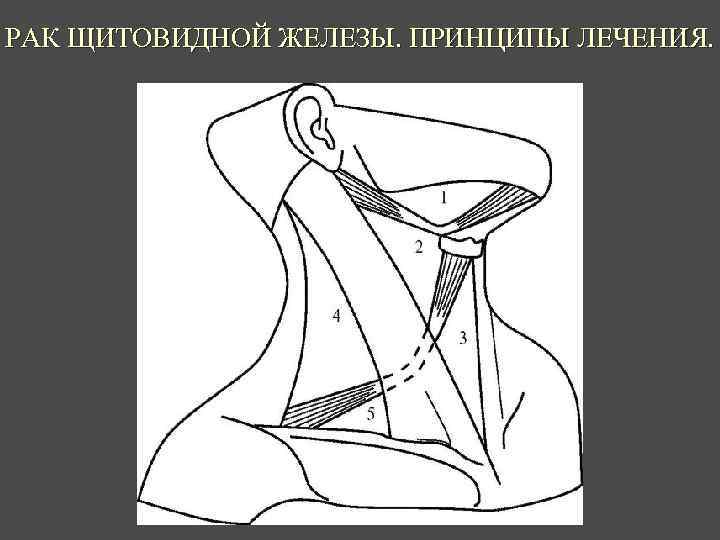

РАК ЩИТОВИДНОЙ ЖЕЛЕЗЫ. ПРИНЦИПЫ ЛЕЧЕНИЯ. Папиллярный рак Фолликулярный рак 1. 2. 3. 4. 5. 6. Хирургическое лечение. Супрессивная терапия тироксином. Лечение радиойдом. Таргетная терапия (нексовар) при резистентности к радиойоду. Повторные хирургические вмешательства (при регионарном метастазировании) Этаноловая деструкция солитарных метастазов. МАРКЕР ПРОГРЕССИРОВАНИЯ: Тиреоглобулин

РАК ЩИТОВИДНОЙ ЖЕЛЕЗЫ. ПРИНЦИПЫ ЛЕЧЕНИЯ. Медуллярный рак 1. 2. 3. 4. Хирургическое лечение. Повторные хирургические вмешательства (при регионарном метастазировании) Лучевая терапия ? Обследование на выявление МЭН 2 А МАРКЕР ПРОГРЕССИРОВАНИЯ: Кальцитонин

РАК ЩИТОВИДНОЙ ЖЕЛЕЗЫ. ПРИНЦИПЫ ЛЕЧЕНИЯ. Недифференцированный рак Плоскоклеточный рак 1. 2. 3. Хирургическое лечение. Лучевая терапия Химиотерапия ПРОГНОЗ – Неблагоприятный, выживаемость менее 1 года после установки диагноза.

РАК ЩИТОВИДНОЙ ЖЕЛЕЗЫ. ПРИНЦИПЫ ЛЕЧЕНИЯ.

РАК ЩИТОВИДНОЙ ЖЕЛЕЗЫ. ПРИНЦИПЫ ЛЕЧЕНИЯ.